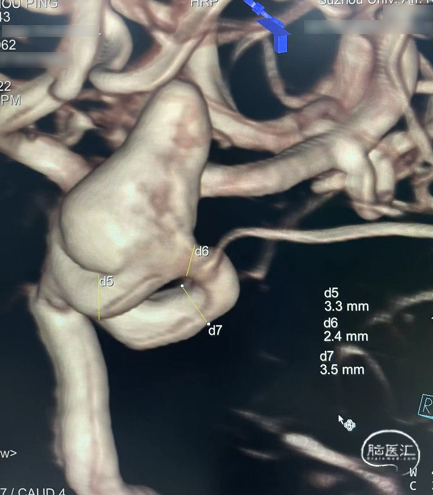

病例2

左侧颈内动脉眼动脉段动脉瘤

术前影像

术后影像

术后6个月随访完全栓塞

术后12个月随访完全栓塞

诊断:左侧颈内动脉眼动脉段动脉瘤,动脉瘤瘤体直径12.8mm,瘤颈直径6.5mm,载瘤动脉远端直径3.3mm,近端直径3.5mm;密网支架落脚于近端较为平直段血管处,直径略大。

处理策略:弹簧圈1枚,1枚如意SM*FDD-425-25mm治疗。